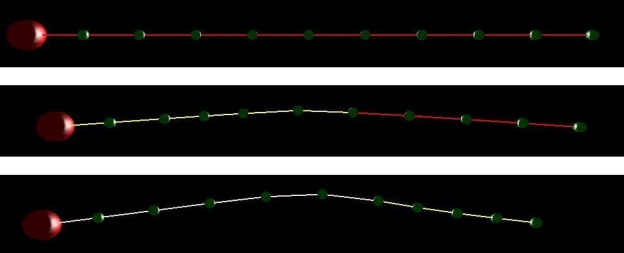

The model was systematically validated through dimensional progression, starting with simple geometries and advancing to anatomically accurate structures:

1D Strand (11 nodes)

Validated electrical wavefront propagation and conduction blockage. The fundamental unit for testing signal transmission.

2D Ring (24–200 nodes)

Demonstrated macro-reentrant circuits and reentry tachycardia. Tests boundary conditions and circular wave propagation.